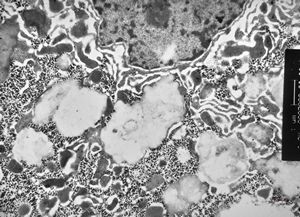

F,32y. | M. Gaucher